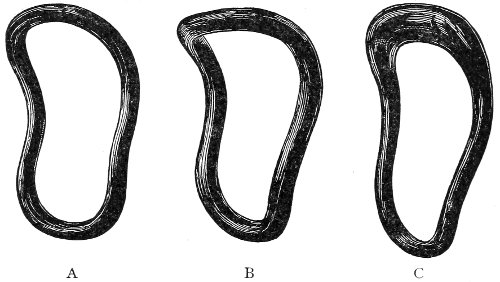

The vagina extends, as a transverse slit in the pelvic floor, upward and backward, approximately in the direction 60 of a line drawn from the ostium vaginæ to the fifth sacral vertebra. It is approximately parallel with the conjugate of the brim, so that when the woman is erect the long axis of the vagina is inclined at an angle of 60° to the horizon. The vagina is not a vertical open tube: it is a slit in the pelvic floor, in health always closed by the accurate apposition of the anterior and posterior walls (Fig. 21). The anterior vaginal wall is about 2½ inches long in a vertical mesial line. The posterior vaginal wall is about 3½ inches long. The vaginal walls are triangular in shape, being broader above than below. The shape of the normal vagina at the pelvic outlet is shown by Fig. 23. The section here shows the vaginal 61 slit of the shape of the letter H. The portions of the slit extending backward and somewhat outward are called the vaginal sulci or furrows. They are directions of diminished resistance in which tears are liable to occur.

Fig. 23.—Section illustrating the characteristic form of the vaginal cleft (Henle): Ua, urethra; Va, vagina; L, levator ani; R, rectum.] 62